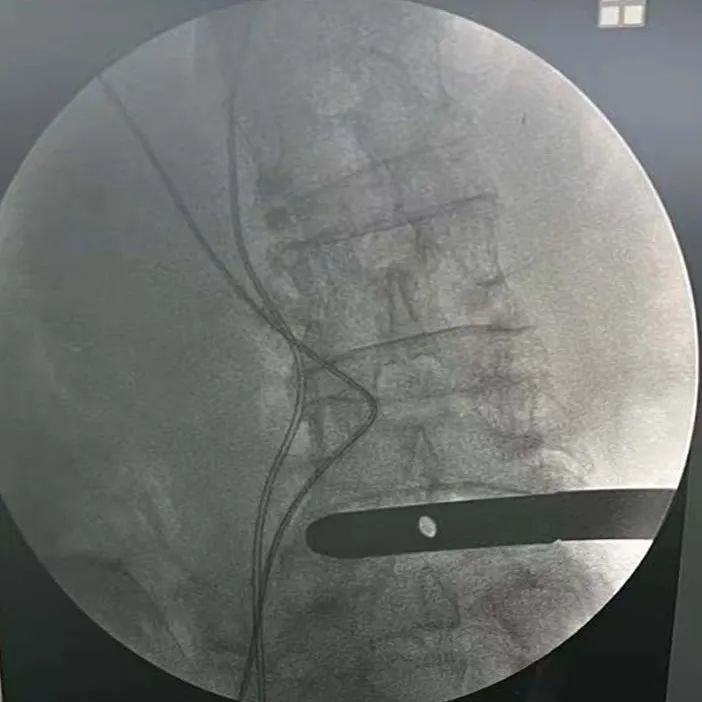

植入(ru)融合器,透視確認融合器位(wei)置——

透(tou)視確認固(gu)定夾——

插片融合器植入前后影像對(dui)比——

椎間隙高度撐開效(xiao)果顯著,椎(zhui)間孔空(kong)間恢復明顯

取(qu)下插(cha)片融合器把持(chi)器,透視(shi)最終效果——